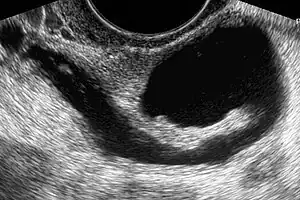

| Left hydrosalpinx on gynecologic ultrasonography | |

Hydrosalpinx may be diagnosed using ultrasonography as the fluid filled elongated and distended tubes display their typical echolucent pattern. However, a small hydrosalpinx may be missed by sonography. During an infertility work-up a hysterosalpingogram, an X-ray procedure that uses a contrast agent to image the Fallopian tubes, shows the retort-like shape of the distended tubes and the absence of spillage of the dye into the peritoneum. If, however, there is a tubal occlusion at the utero-tubal junction, a hydrosalpinx may go undetected. When a hydrosalpinx is detected by a hysterosalpingogram it is prudent to administer antibiotics to reduce the risk of reactivation of an inflammatory process.